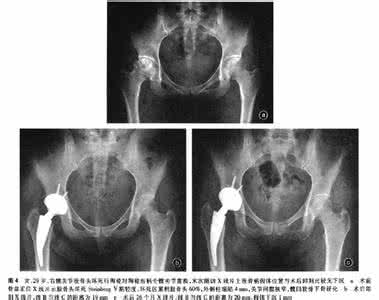

E 图2 股骨头标本外观的及影像学测量图

Figure 2 Appearance and

measurements of the femoral head revealed on radiology

图注:图A为术中截取的股骨头外观;B为从标本正中沿其冠状面用电动摆锯纵行剖开,确定股骨头中心点,沿股骨颈纵轴连线至股骨头顶点通过中心点(X),垂直于X的连线(Y)同时通过中心点;C-F分别为股骨头剖面X射线图,CT图,设计简图,Digimizer软件显示图:图中股骨头中心点沿X轴至股骨头顶点的距离确定为b,股骨头中心点延Y轴至股骨头外侧顶点的距离为c,最后确定a,其与b和c间夹角均为45°。a,b,c分别代表股骨头塌陷后中间、内侧及外侧的实际高度。

应用图像测量分析软件Digimizer V3.8.1.0(Med Cale Software,USA)在骨盆正位X射线片上及双髋关节CT上测量患侧及健侧股骨头中心点距3个不同位置股骨头顶点的距离(图2C-F)。患侧股骨头X射线线上中间、内侧及外侧的高度分别用a′,b′,c′表示;患侧股骨头CT上中间、内侧及外侧的高度分别用 a′′,b′′,c′′表示;健侧股骨头X射线线上中间、内侧及外侧的高度分别用a1,b1,c1表示;健侧股骨头CT上中间、内侧及外侧的高度分别用a2,b2,c2表示。 1.12 结局指标